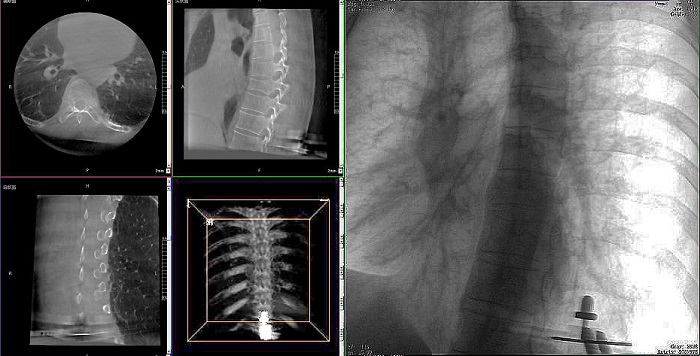

患者:71歲,男性,胸8椎體壓縮性骨折

術式:機器人輔助經皮釘棒系統復位內固定手術

③機器人輔助胸椎手術操作難點之精準置釘

傳統開放手術中,胸椎的手術視野相對受限,螺釘的置入主要依賴于醫生的經驗和手感,存在一定的主觀性。

普愛醫療手術導航定位系統解決方案

普愛醫療骨科手術機器人的高精度機械臂,按照規劃好的路徑及角度,自動精準定位穿刺點,醫生打入克氏針后,正側位圖像顯示精度滿足預期,醫生完成置釘等后續手術操作。